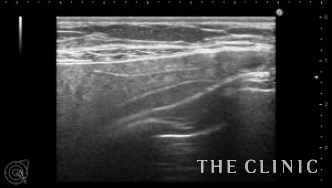

本日紹介する方は左胸の痛みで来院、見た目や触診では問題ありませんでしたが、エコー検査で左胸のバッグが破損していました。エコー所見です。右は軽度のカプセル拘縮を認めますが、左は破損してカプセル内にシリコンが漏れていました。腋の下からバッグを取り出しましたが、左のカプセル内にはシリコンが漏れていました。

バッグの破損があると術後にカプセル内にリンパ液が貯留する場合がありますが、

1週間後のエコーではリンパ液の貯留もなく問題ありませんでした。バッグの破損は自覚症状がない場合も多いので、定期的にエコー検査をするべきだと思います。